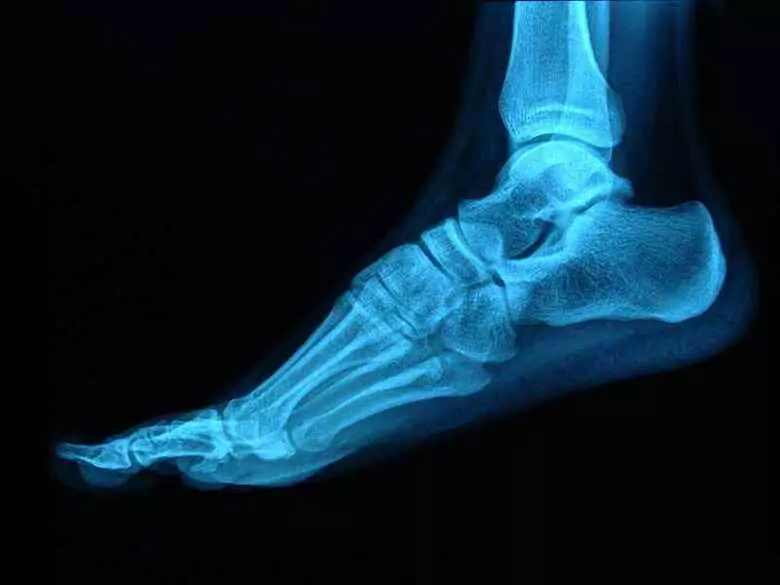

Idealna stopa u człowieka nie istnieje. Jednak nieodpowiednie jej ułożenie i niewłaściwa biomechanika chodu mają wpływ również na pozostałe narządy w organizmie. Optymalne ułożenie stopy pozwala na właściwe jej funkcjonowanie. Kiedy występują nieprawidłowości organizm musi sobie je jakoś zrekompensować. Czy chodzenie boso jest zdrowe podpowiada fizjoterapeuta.